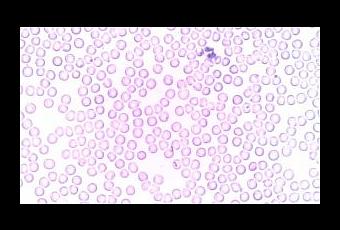

La leucocitosis se puede definir como el aumento de leucocitos en la sangre, unas células también conocidas con el nombre de glóbulos blancos que se ocupan de luchar contra las enfermedades.